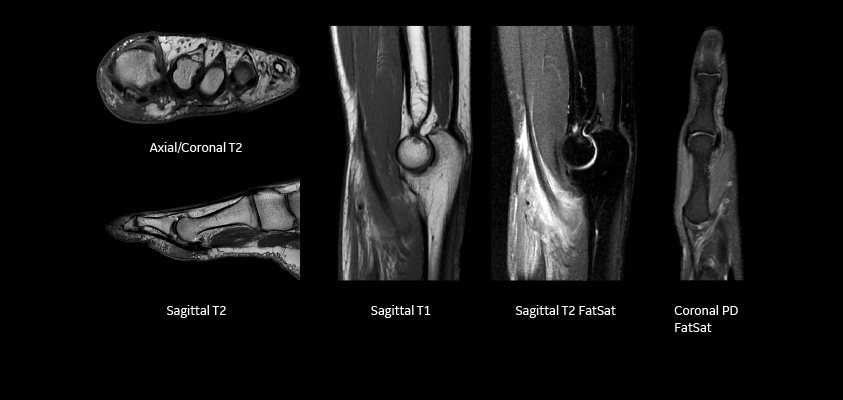

Whether it’s your brain, spine, joints, or soft tissues, the 1.5T MRI produces sharp images that help detect problems early.

Joint & Bone Conditions

Sports injuries, arthritis, ligament tears